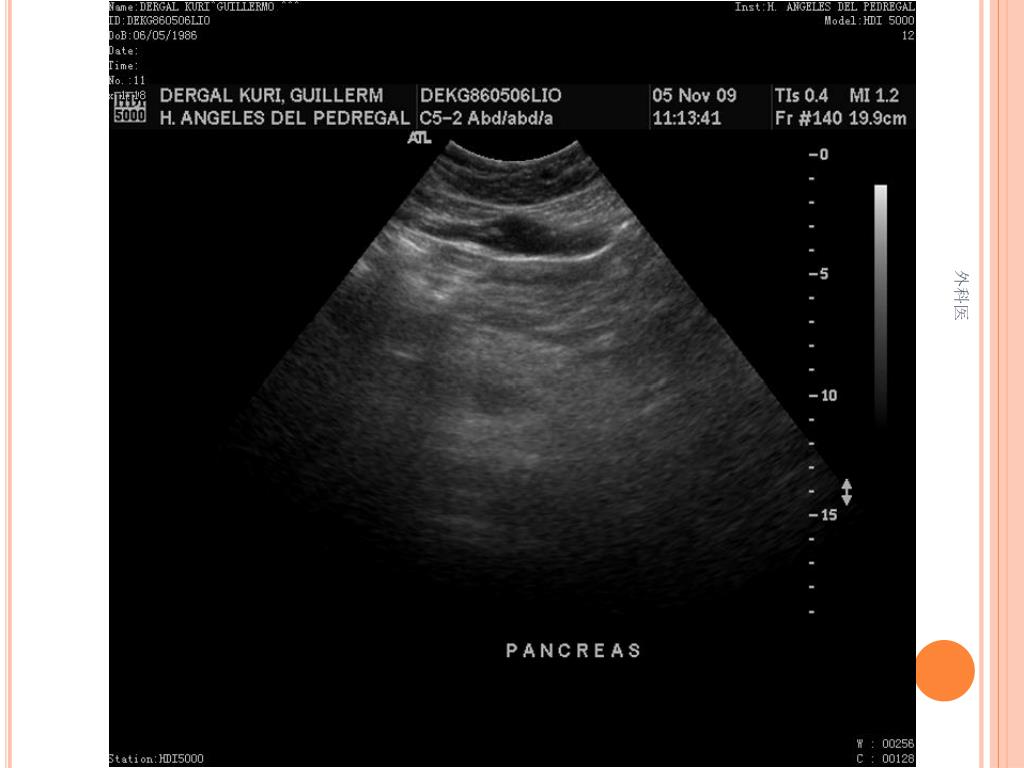

44. Tips • Leucocitos Mas de 20000/ml • Mas de 20% de la apéndices no se llenan con el bario por enema. • USG sensibilidad del 85% y Especificidad de mas 90% para Apendicitis Aguda. • TAC de Abdomen cortes de 5mm, sensibilidad y especificidad del 90% para dolor abdominal. • Analisis de 75000, taza de apendice negativa de 6% Hombres y 13% Mujeres 外科医